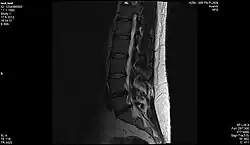

Magnetická rezonance (též MR, MRI, z anglického „magnetic resonance imaging“) je zobrazovací technika používaná především ve zdravotnictví k zobrazení vnitřních orgánů lidského těla. Pomocí MRI je možné získat řezy určité oblasti těla, ty dále zpracovávat a spojovat až třeba k výslednému 3D obrazu požadovaného orgánu. Magnetická rezonance využívá silné statické magnetické pole (řádově jednotky T) a elektromagnetické vlnění (s frekvencemi v řádu desítek až stovek MHz). Na rozdíl od CT vyšetření, které je s MR někdy alternativní, nenese žádná rizika způsobená ionizačním zářením (nulová radiační zátěž). Nevýhodou vyšetření MR je určitá hlučnost zařízení. Podstatou odlišení jednotlivých tkání a patologií je jejich rozdílné chování při stejném vnějším působení. Vyšetření se provádí bez kontrastní látky nebo s ní (např. gadolinium vpichem do žíly).

Výhodou MRI vůči ostatním zobrazovacím metodám v diagnostické radiologii je větší přesnost při zobrazení většiny orgánů, jež je důsledkem rozdílné intenzity signálu u odlišných měkkých tkání. Navíc toto zobrazení probíhá bez možného škodlivého ionizujícího záření. Některé orgány jako nervy či mozková tkáň bylo možné neinvazivně zobrazovat až právě pomocí MRI. Díky rozsahu nastavení vyšetření je možné dosáhnout rozlišení, které dalece přesahuje možnosti rentgenu či CT. Dalšího zlepšení může být ještě dosaženo podáním kontrastní látky, která pomůže odhalit přítomnost zánětů nebo nádorových tkání.